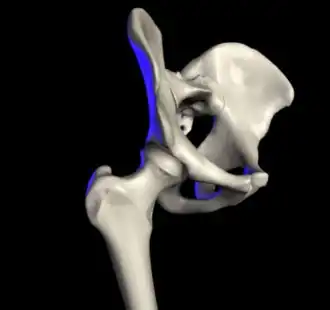

![]() Компьютерная модель сустава. | |

Та́зобе́дренный суста́в (лат. articulatio coxae) — чашеобразный, многоосный сустав, образованный полулунной поверхностью вертлужной впадины тазовой кости и суставной поверхностью головки бедренной кости. Вертлужная губа, сращённая с краем вертлужной впадины, углубляет последнюю.

Анатомия

Суставная капсула к тазовой кости прикрепляется по окружности вертлужной впадины, оставляя вертлужную губу внутри полости сустава. К бедренной кости капсула прикрепляется спереди вдоль межвертельной линии, сзади — немного отступая кнутри от межвертельного гребня. Таким образом, шейка бедра располагается в суставной полости.

Связка головки бедра (лат. ligaméntum cápitis fémoris), находящаяся внутри суставной капсулы, препятствует чрезмерному приведению и наружной ротации бедра. Кроме этой связки тазобедренный сустав укреплён несколькими толстыми, прочными связками, расположенными как в толще капсулы, так и на её поверхности, а именно: